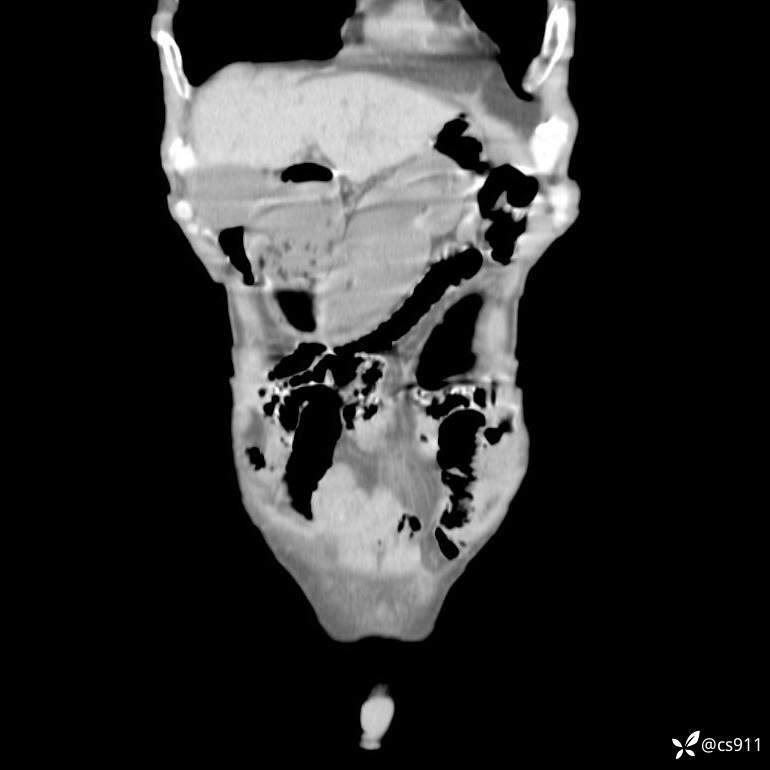

急腹症之急诊CT,原因?答案公布

男,77岁,腹痛、腹胀伴恶心呕吐1天。呕吐胃内容物,非喷射性呕吐,有咖啡色样胃内容物,诉有胃穿孔病史。查体:全腹平,下腹部压痛,全腹无反跳痛,叩诊呈浊音,移动性浊音阴性,肠鸣音减弱,1-2次/分。肛检:直肠未扪及明显肿物,可触及大量粪块。

T 36.6℃ P 80次/分 R 26次/分 BP 100/60mmHg

白细胞(WBC) H 14.55 10e9/L 4-10

中性粒细胞百分率(NEUT%) H 85.7 % 40-75

血淀粉酶(AMY) HH 1859 U/L 35-135

癌胚抗原(CEA) H 27.44 ng/ml 0-5

呕吐物 潜血试验 * 阳性 阴性

患者轮椅入室检查神志清楚, 能配合摆位和呼吸